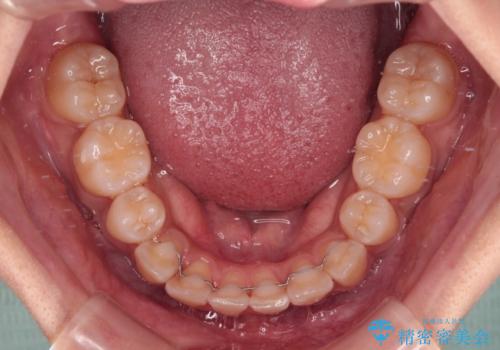

- 前歯のデコボコやクロスバイトと上顎の前突感による口の閉じにくさを気にして来院された患者様です。

目立たない装置を希望されたので、上顎が裏側装置のハーフリンガルを選択し、上下左右の小臼歯(計4歯)を抜歯して矯正治療を行うこととしました。

表側のワイヤー矯正に比べると治療期間は長く、費用も高額となりますが、どうしても目立たせたくないという方にはお勧めの抜歯矯正です。